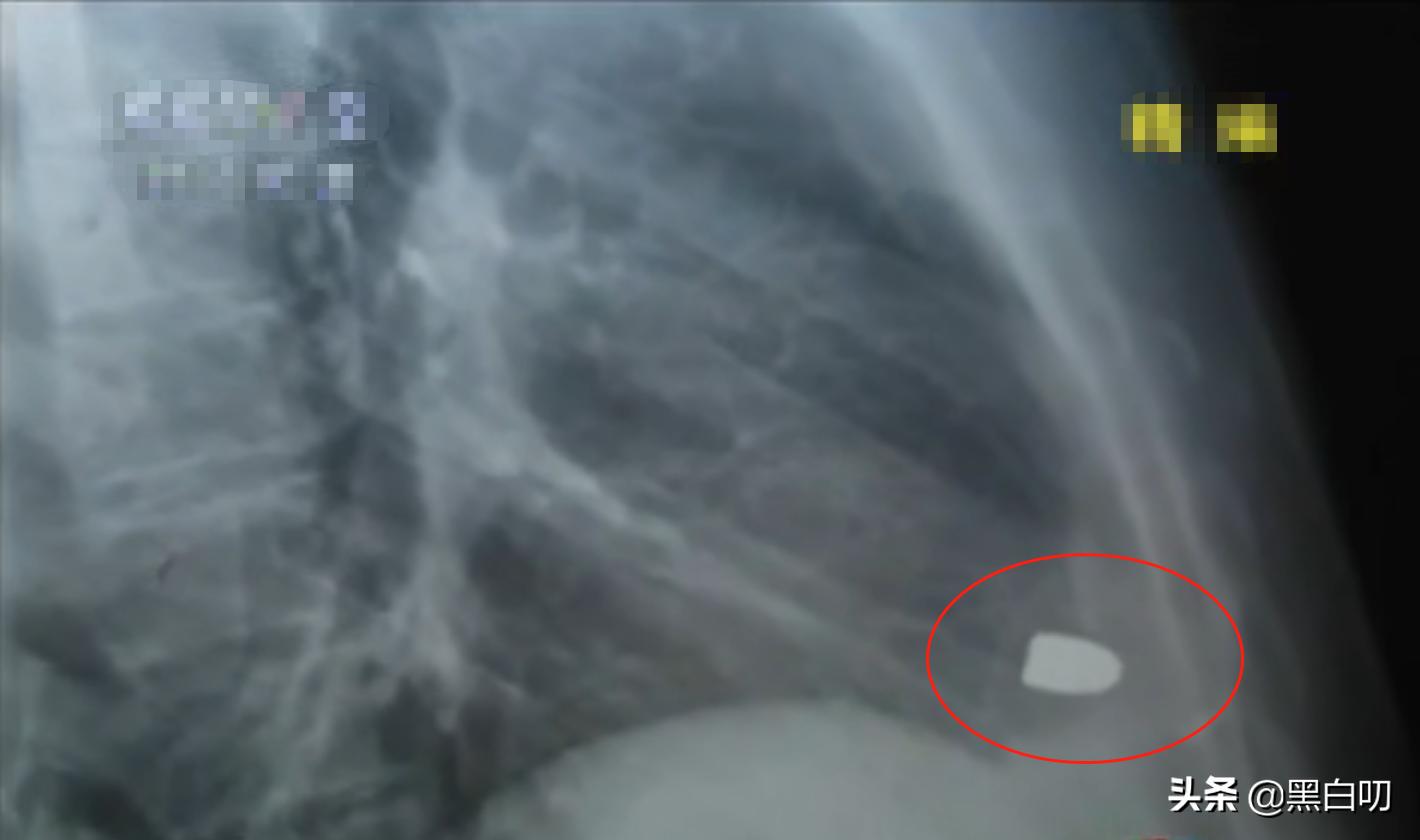

经过检查后,医生发现X光片里居然有一个金属状的白色亮点。

为了让符桂林放宽心医生还特意让他脱了衣服检查,并且也照了个侧方位的X光片,等结果出来之后惊呆了在场的所有人。

符桂林的心脏部位居然有一颗*弹子**!并且那颗*弹子**还随着心脏同步跳动!

位于符桂林心脏部位的*弹子**

之后经过医生对片子大致地测量,*弹子**的长度约为13毫米,直径约为9毫米,确实是一颗手枪的*弹子**。

符桂林心脏部位的*弹子**